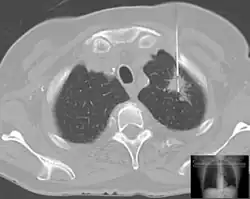

| Lung | Biopsies of the lung can be performed in a variety of ways depending on the location. |